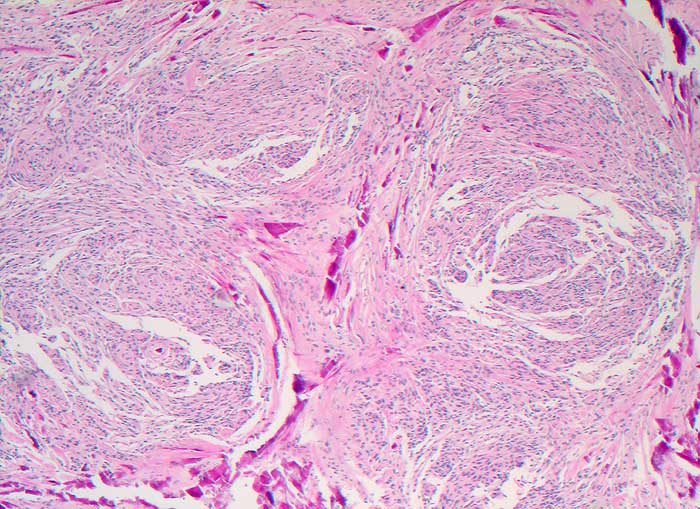

Abstriche und Waschflüssigkeit von Meningeomen sind meist auffallend zellreich. Die Zellen sind in pseudoepithelialen Verbänden gelagert. Charakteristisch sind Psammomkörperchen und zwiebelschalenartig geschichtete meningotheliale Zellkomplexe. Bei bestimmten Meningeomsubtypen sind diese Zellkomplexe jedoch nicht leicht auffindbar. Die Kerne enthalten gelegentlich intranukleäre Vakuolen. Die Zellen anaplastischer Meningeome sind stärker dissoziiert, die Kerne sind hyperchromatisch und pleomorph, Mitosen sind vermehrt.